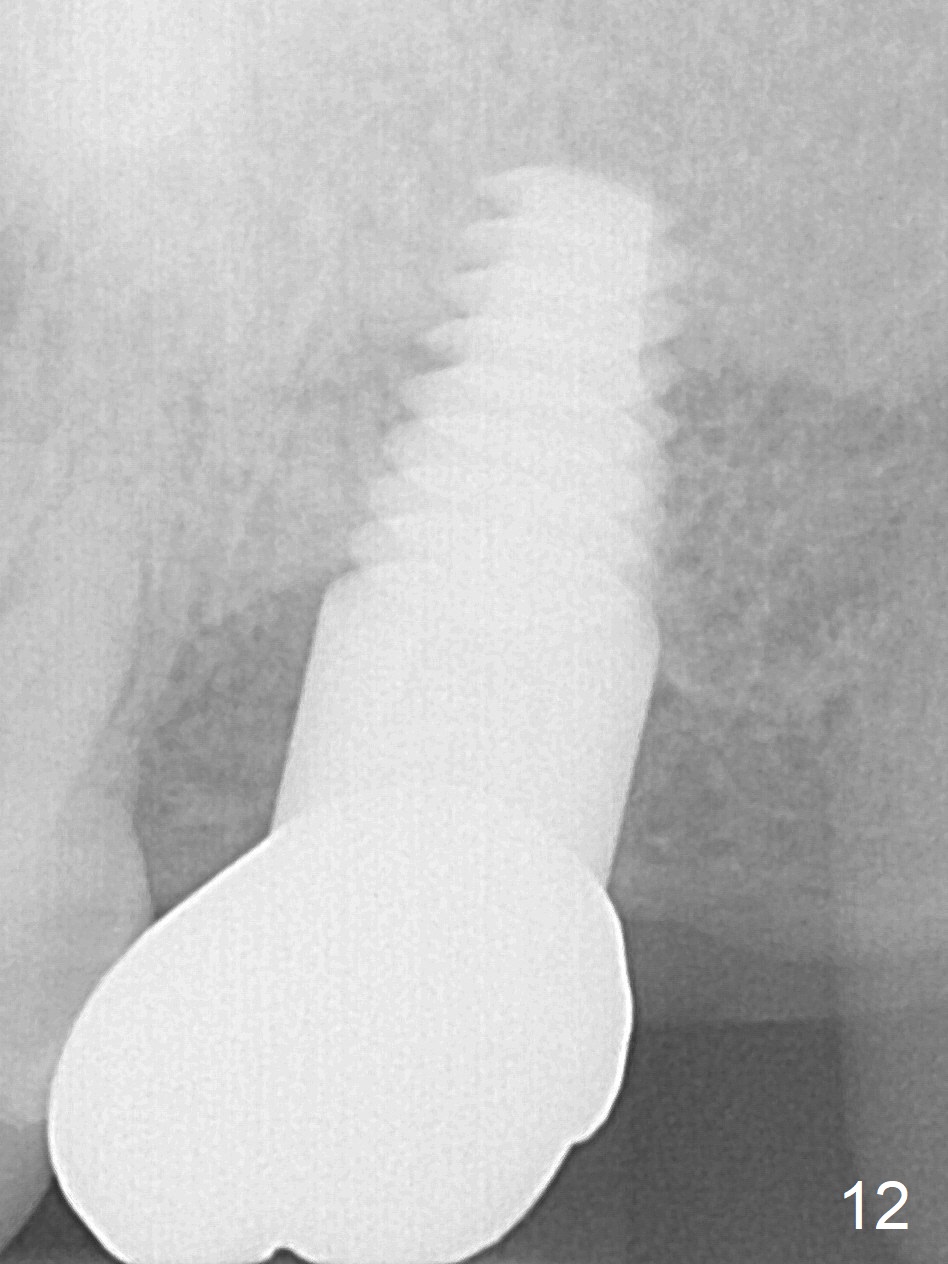

There is no bone loss 17 months post cementation (Fig.12). The patient reports that he has to keep cleaning well to prevent discomfort locally. Clinically, the gingiva is healthy around the implant crown. No bone loss is around the implant 3 years 8 months post cementation (Fig.13), but the natural teeth are not so fortunate (Fig.14).